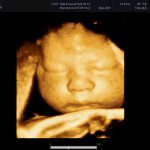

маленький малыш